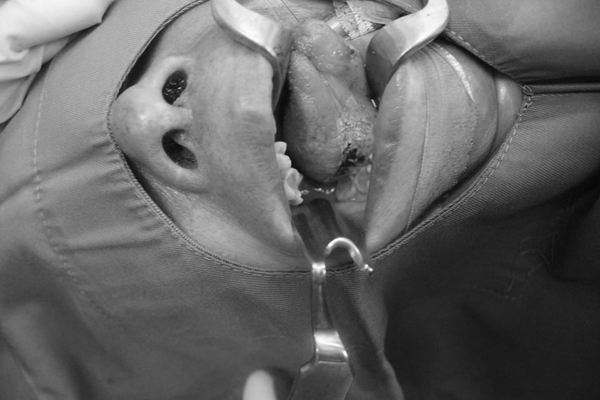

Hình ảnh mảng trắng dày bao phủ dưới lưỡi phải bệnh nhân

Các bác sĩ khoa Tai mũi họng khám và phát hiện có mảng bạch sản dưới lưỡi bên phải, kích thước khoảng 3 cm. Bệnh nhân được chỉ định phẫu thuật cắt hớt niêm mạch lưỡi bằng laser để loại bỏ tổ chức bạch sản.